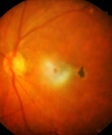

Diabetic Retinopathy

Eales Disease

Macular Degeneration (ARMD)

Retinal Detachment

Retinitis Pigmentosa

Uveitis